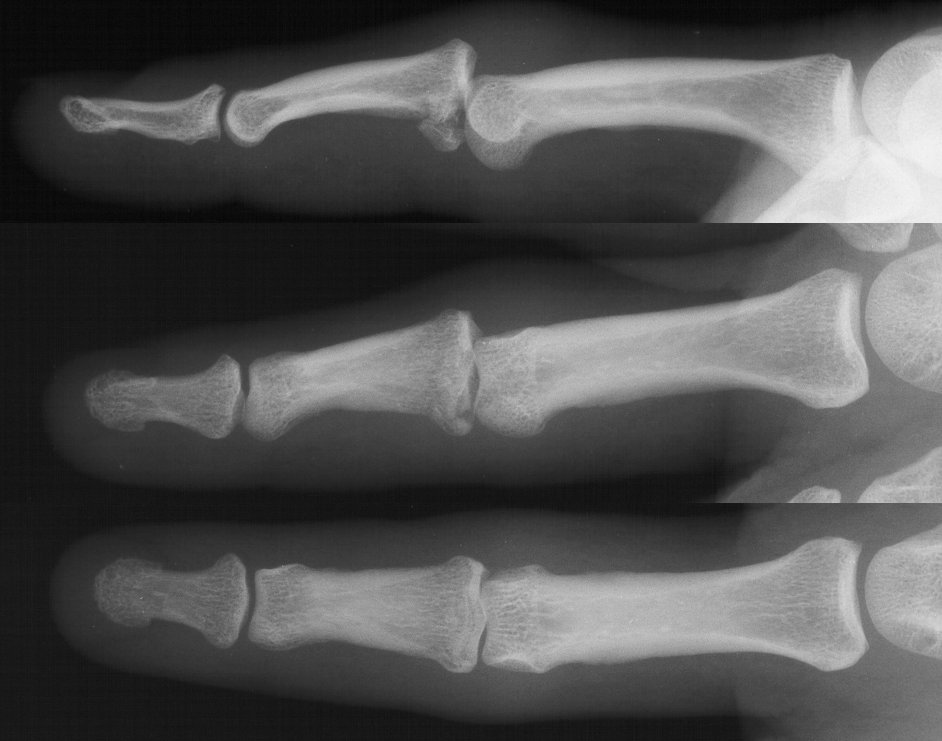

This gentleman sustained a comminuted proximal interphalangeal fracture dislocation.

The palmar base of the middle phalanx is in at least three thin fragments. The palmar ulnar condyle of the proximal phalanx head has irregular sections of cartilage loss.